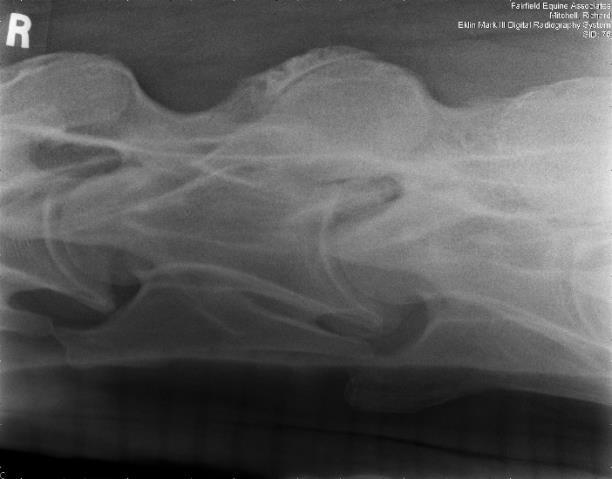

The development and advancement of digital radiography has allowed for diagnostic field radiographs of the neck and some parts of the thoracolumbar spine. Lateral images of the cervical spine may demonstrate the presence of osteoarthritis, vertebral anomalies, and abnormalities of the vertebral canal, such as stenosis. One can also acquire very diagnostic oblique images of the cervical articular processes with practice (Figures 2A and 2B).

RFigure 2A: Field radiograph using portable machine and DR technology demonstrating enlargement of an articular process joint. Cranial is to the left.

Fig. 2A: Field radiograph using portable machine and DR technology demonstrating enlargement of an articular process joint. Cranial is to the left.

Image courtesy of Dr. Richard D. Mitchell.